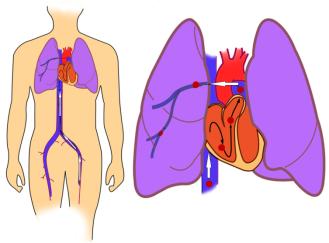

六、小小肺栓可致命

下肢深静脉血栓的急性期并发症,血栓在腿部形成后,如果发生破碎,从下肢静脉脱落下来成为栓子(图7),顺着静脉血流回流到心脏,就像河里的融冰顺着血流流入大海一样。这些栓子并不会止步于心脏,而是被心脏排入肺动脉,形成肺栓塞,也称肺梗(图8)。

图7 深静脉血栓脱落后随血液回流

图8 栓子经过心脏,最终栓塞于肺动脉

如果栓子的体积比较小,那它就会卡在远端的肺动脉分支上,引起相应肺脏区域的缺血和坏死,这个区域相对较小,病人无明显异常或只有咳嗽、胸部不适等轻微症状。但是如果栓子的体积较大,卡在肺动脉较大的分支甚至主干上,或者栓子虽小但数量很多,就会造成大面积的肺脏梗死,导致胸闷、胸痛、气急、咯血、呼吸衰竭等严重症状,甚至因为大块栓子猛然间堵塞了人体血液循环的核心主干道,而导致猝死。

每年,国内外都会发生大量肺栓塞导致的猝死,比如,产妇发生下肢深静脉血栓和肺栓塞发生猝死,遽然永别嗷嗷待哺的初生幼儿,喜剧瞬间变悲剧。因此,肺栓塞是一种极为危重的并发症,必须做好高危人群的防治工作。